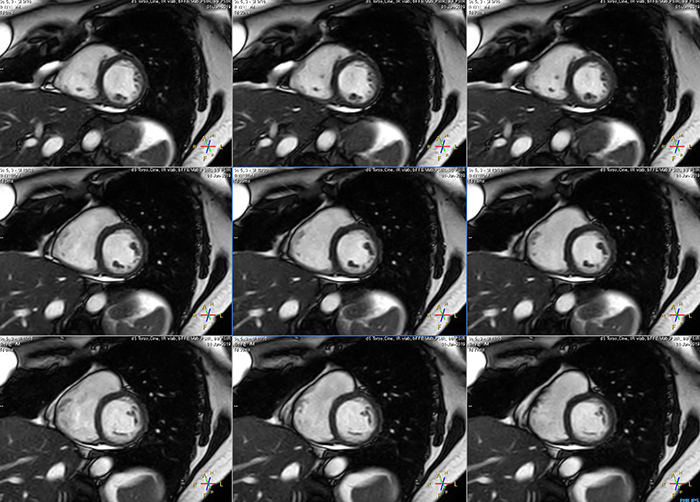

These are some images of a cardiac cine scan with a short breath-hold time. A high temporal resolution provides a smooth cine, which helps in assessing heart function. Ingenia Ambition.

Avila says that Compressed SENSE allows them to reduce breathhold time to 3 to 4 seconds in cardiac cine scans. “At the same time, we can now – based on cardiac frequency – obtain as many as 30 to 40 cardiac phases without sacrificing resolution, while before Ingenia Ambition, we were acquiring only 20 phases.

“This ability to use Compressed SENSE for obtaining higher temporal resolution translates to a much smoother cine. This allows me to better assess heart function,” Dr. Peña says.

The images obtained with Ingenia Ambition show large coverage and high uniform signal. More vessels are visible than in a previous exam of the same patient on Achieva. The movies show a higher temporal resolution in the Ambition acquisition than in a previous Achieva 1.5T exam. Both exams use a FOV of 300 mm and voxel height and width of 0.78 mm.

Achieva 1.5T

2:30 min. TE 1 ms, TR 4 ms

Ingenia Ambition

4D Trak XD 1:54 min. TE 1ms, TR 3ms